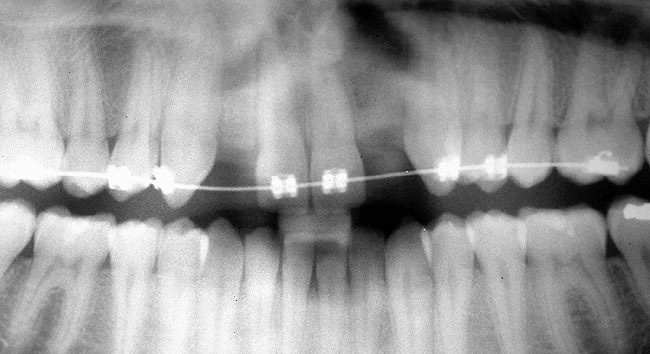

Periapical radiographs were taken to help determine the mesial-distal inclinations of the adjacent tooth roots (Figure 1). The radiographs revealed a serious issue, convergent roots for the right canine and right central, which eliminated that area as a potential implant-receptor site. The space between the left central and canine teeth was minimal, although the roots were relatively parallel. Clinical examination (manual palpation of the root eminences superiorly to the vestibule on the right side) confirmed the root convergence (Figure 2). The flat, wide zone of the keratinized tissue and lack of interdental papilla was evident for the missing right lateral incisor. There was a marked difference in clinical appearance for the left lateral, which could impact the eventual plan of treatment (Figure 3). Other significant clinical findings included bilateral facial bone concavities, which existed as a result of the congenitally missing tooth roots. As a diagnostic cue to the underlying bone topography, it is important to follow the demarcation between attached and unattached gingival tissue, and note the crestal width of the available keratinized tissue (Figure 4).

Figure 1  PRE-TREATMENT DIAGNOSTICS Pretreatment radiographs revealed convergent roots for the right canine and right central.

Figure 1